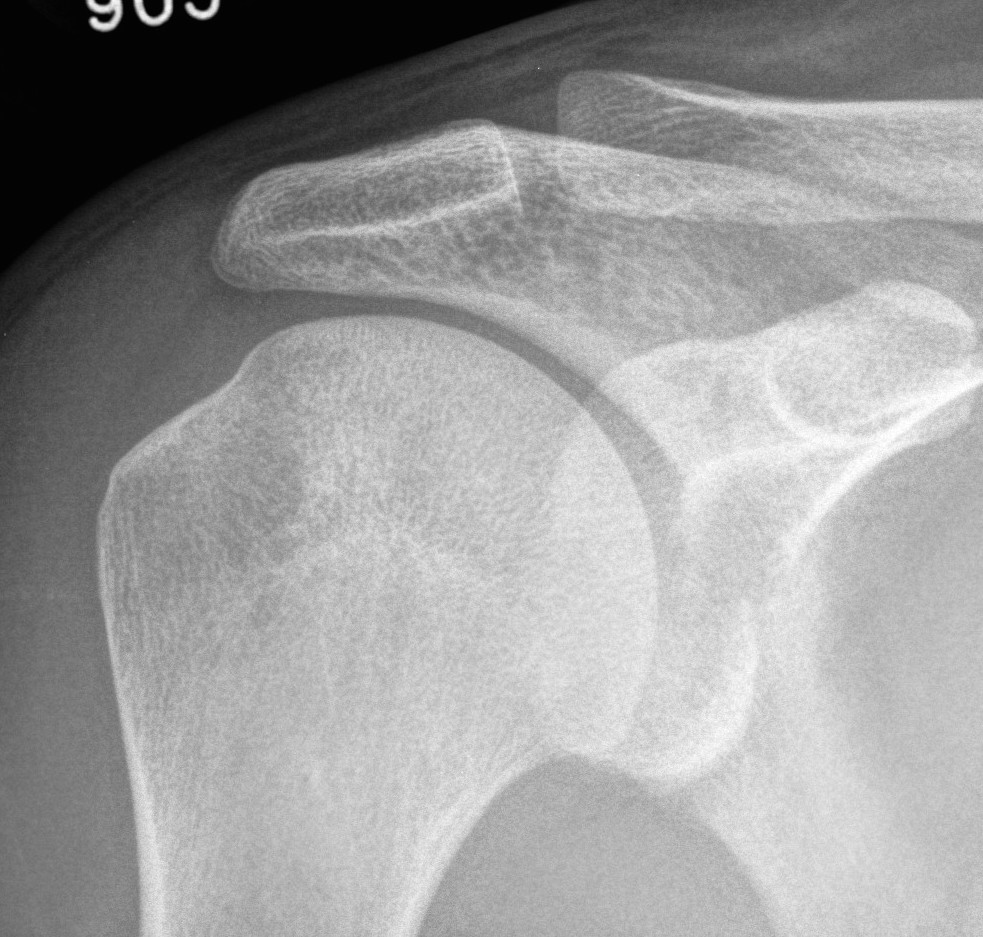

Greater tuberosity fractures

Indications

- > 5 mm displacement

Management

- ORIF with plate

- screw + suture repair

- screw alone in young patient